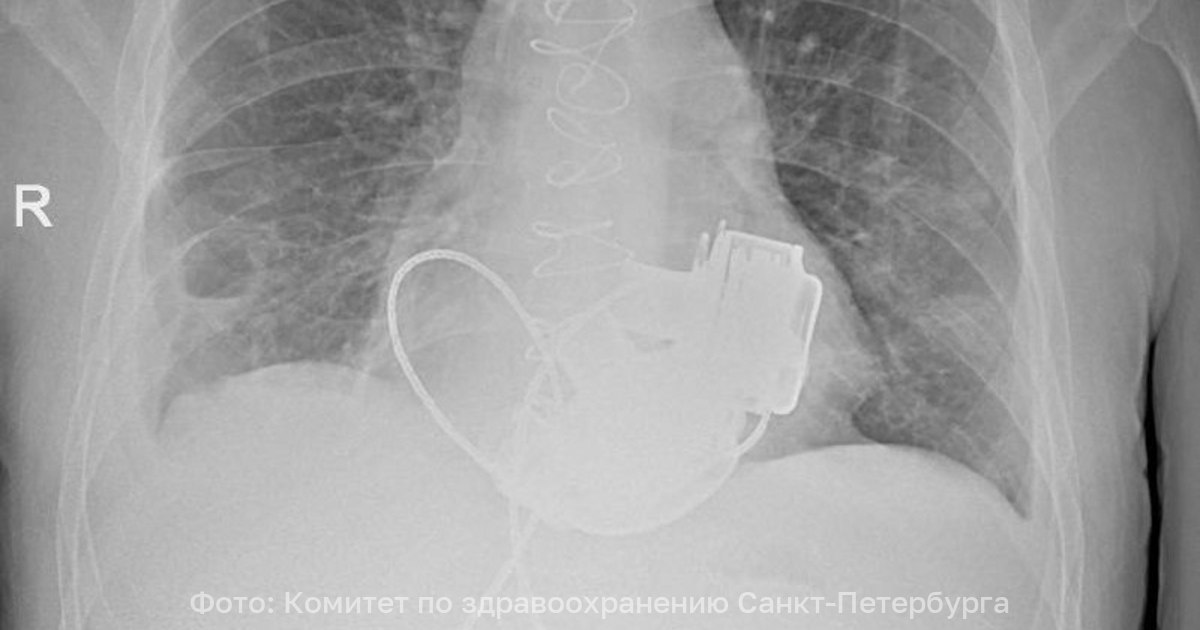

Пациента без пульса выпишут из больницы в Петербурге Уникальный пациент которому впервые в России имплантировали сразу два искусственных желудочка сердца готовится к выписке из Мариинской больницы в Санкт Петербурге В Мариинской больнице готовится к выписке уникальный пациент который с недавних пор живет без пульса В конце ноября 2025 года ему впервые в России имплантировали сразу два искусственных желудочка сердца левое и правое рассказали в комитете здравоохранения города Операцию провели в конце ноября 2025 года 36 летнего петербуржца экстренно госпитализировали с тяжелейшими диагнозами кардиомиопатией и терминальной сердечной недостаточностью По словам врачей функциональные показатели работы сердца были критическими и находились на уровне характерном для мертвого человека Решение о проведении сложнейшего вмешательства принял главный врач Мариинской больницы Игорь Реутский Операция длилась около четырех часов Самым трудным этапом стало согласование и синхронизация работы двух искусственных желудочков Сейчас состояние пациента стабилизировано Он проходит завершающий этап реабилитации и готовится к выписке Фото пресс служба комитета по здравоохранению Петербурга Подпишитесь на ivbg ru Ivbg в Max

В Санкт Петербурге врачи Мариинской больницы выписали домой пациента у которого пока нет пульса Он живет с механическим сердцем Уникальную операцию отцу двоих детей провели три месяца назад Больному впервые в России имплантировали сразу два искусственных желудочка Это временная мера перед трансплантацией У Антона Павлова теперь искусственное сердце которое работает от двух приборов на аккумуляторах Есть контроллер аппарат на который выводятся основные функции показывается количество оборотов в минуту пульсовой индекс мощность те параметры которые мы контролируем объяснила заведующая 1 м кардиологическим отделением СПб ГБУЗ Городская Мариинская больница Наталья Платонова Носить две сумки необходимо постоянно и не забывать заряжать аккумуляторы каждые 17 часов Но Антон уже привык Он понимает что это спасло ему жизнь Я рад что здоров что врачи меня спасли Спасибо им В принципе все хорошо Конечно риски были думал о рисках как все получится Но выбора не было Если бы не сделали операцию то я бы уже умер рассказал обладатель искусственного сердца Антон Павлов Антону всего 36 лет но в петербургскую Мариинскую больницу он поступил в терминальной стадии сердечной недостаточности с множеством осложнений Пациент с рецидивирующей тромбоэмболией У него постоянно образовывались тромбы которые стреляли в органы в легкие ему было трудно дышать у него развилась дыхательная недостаточность тяжелая на фоне тяжелой сердечной недостаточности говорит врач кардиолог СПб ГБУЗ Городская Мариинская больница Кристина Смелкова В такой ситуации спасти может только пересадка донорского сердца но провести трансплантацию оказалось невозможно из за противопоказаний Поэтому кардиохирурги решились заменить оба желудочка на механические Уникальная операция длилась четыре часа Пришлось отключить сердце пациента запустить искусственную систему кровообращения и имплантировать одновременно два механических насоса которые нужно было еще и правильно наладить Была проблема синхронизировать два искусственных левых желудочка которые у человека синхронизируются на уровне головного мозга вегетативной нервной системы А здесь две железки которые мы должны были сами искусственно садаптировать друг к другу поделился главный кардиохирург Санкт Петербурга академик РАН Геннадий Хубулава Операцию провели три месяца назад много времени понадобилось на восстановление Антону пришлось привыкать к гулу механических насосов которые теперь у него вместо сердца В принципе никаких ограничений у меня нет Я хожу я бы бегал если бы не сумки Чувствую себя прекрасно сказал Антон Ходить с сумками Антону придется недолго ведь через несколько месяцев он вернется в Мариинскую больницу чтобы получить донорское сердце Тогда и пульс к нему вернется